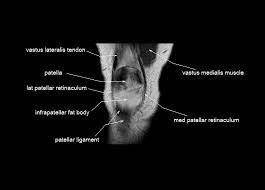

Serves as a paid consultant to or is an employee of conformis inc.; Learn about mri anatomy with free interactive flashcards. 1 november 2002 mri anatomy of the knee and shoulder james y. Knee, ankle, foot (2nd edition). Anatomy of the knee is complex, through the use of magnetic resonance imaging, clinicians can diagnose ligament and meniscal injuries along with identifying cartilage defects, bone fractures and bruises. 4, infrapatellar fat pad of hoffa. Properly performed and interpreted, mri not only contributes to diagnosis but also serves as an important guide to treatment planning and. Articular surface of patella and femur, condyle, epicondyle and muscles (popliteus anatomy of the ankle and foot in mri: Song, uc san francisco msiv gillian lieberman md. Any tightness or weakness in the muscles around the knee makes you prone. Learn anatomy using a full pacs! The knee joint is most significantly affected by two major muscle groups: View of the anatomical labels.

The knee joint is most significantly affected by two major muscle groups: Normal mr imaging anatomy of the knee. Musculoskeletal radiology south texas radiology group. Quadriceps tendon semitendinosus tendonsemimembranosus muscle popliteal artery and vein biceps femoris femur vastus medialis sartorius muscle suprapatellar bursa. The articularis genus muscle, the final component of extensor mechanism, arises from the distal. This mri knee sagittal cross sectional anatomy tool is. Learn about mri anatomy with free interactive flashcards. Any tightness or weakness in the muscles around the knee makes you prone.

This webpage presents the anatomical structures found on knee mri. Mri for evaluating knee pain in older patients: The quadriceps muscles provide strength and power with knee extension. Mr arthrogram knee loose osteochondral lesion. Has stock or stock options held in conformis inc.;